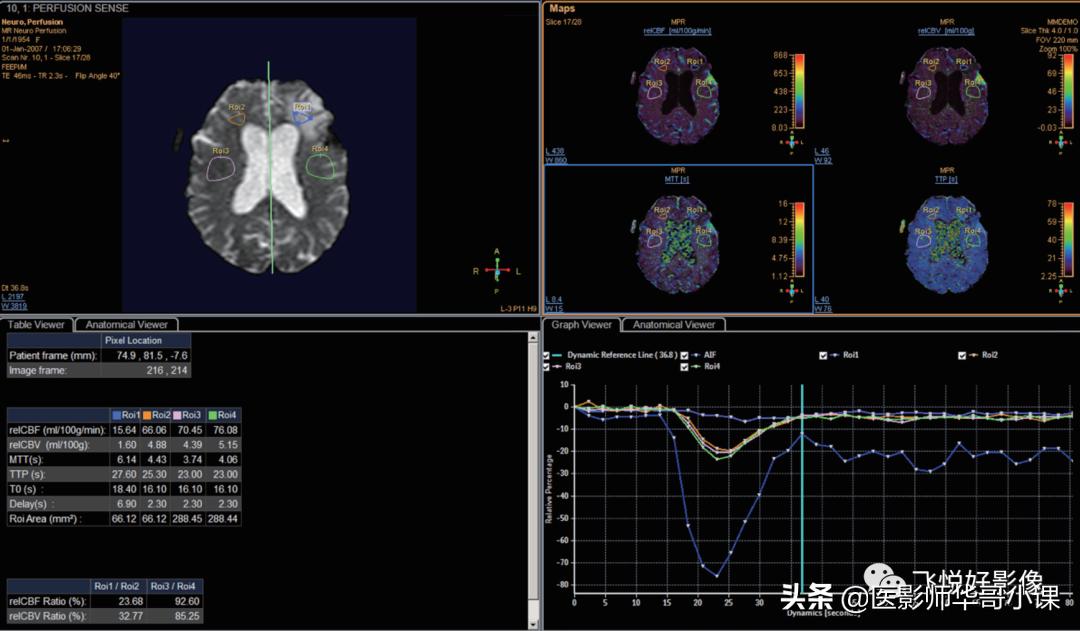

ROI数据会相应出现,图14左下方为表格形式,右上方为绘图形式,右下方为曲线形式。

图14.ROI数据